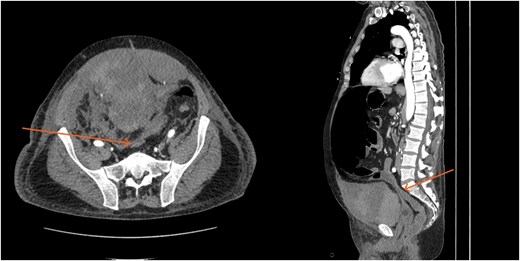

By hospital day 6, the patient’s condition improved. He was weaned from mechanical ventilation, his renal function improved (creatinine declined to 0.7 mg/dl), and hemoglobin stabilized at 8.4 gm/dl. The patient was clinically stable, and on hospital day 8, he was set up for discharge to a rehabilitation institution. However, on this day, he developed generalized abdominal pain associated with tachycardia, pulse = 118, and leukocytosis (white blood cells = 14.8 × 109/l). Physical exam revealed a distended abdomen with diffuse tenderness and sluggish intestinal sounds. A CT scan showed a large volume of pneumoperitoneum, minimal free fluid, and mildly dilated small bowel loops, consistent with a hollow viscus perforation with no identifiable source of perforation (Fig. 5) and a compression of rectosigmoid region against sacral promontory by the enlarged hematoma (Fig. 6). The right colon was decompressed compared with the prior study, and the RSH size remained unchanged, but there was progression of VTE burden. Prior to the acute deterioration, the patient had intermittently reported mild abdominal discomfort, which was initially attributed to the known RSH. There were no clinical signs suggestive of bowel obstruction, such as vomiting or significant abdominal distension. While the patient noted some degree of constipation, he reported that this was consistent with his baseline bowel habits and did not raise concern for new pathology.

CT scan demonstrating pneumo-peritoneum (arrow), indicative of a hollow viscus perforation.

CT scan demonstrating compression of large bowel (arrows) by the enlarged hematoma.